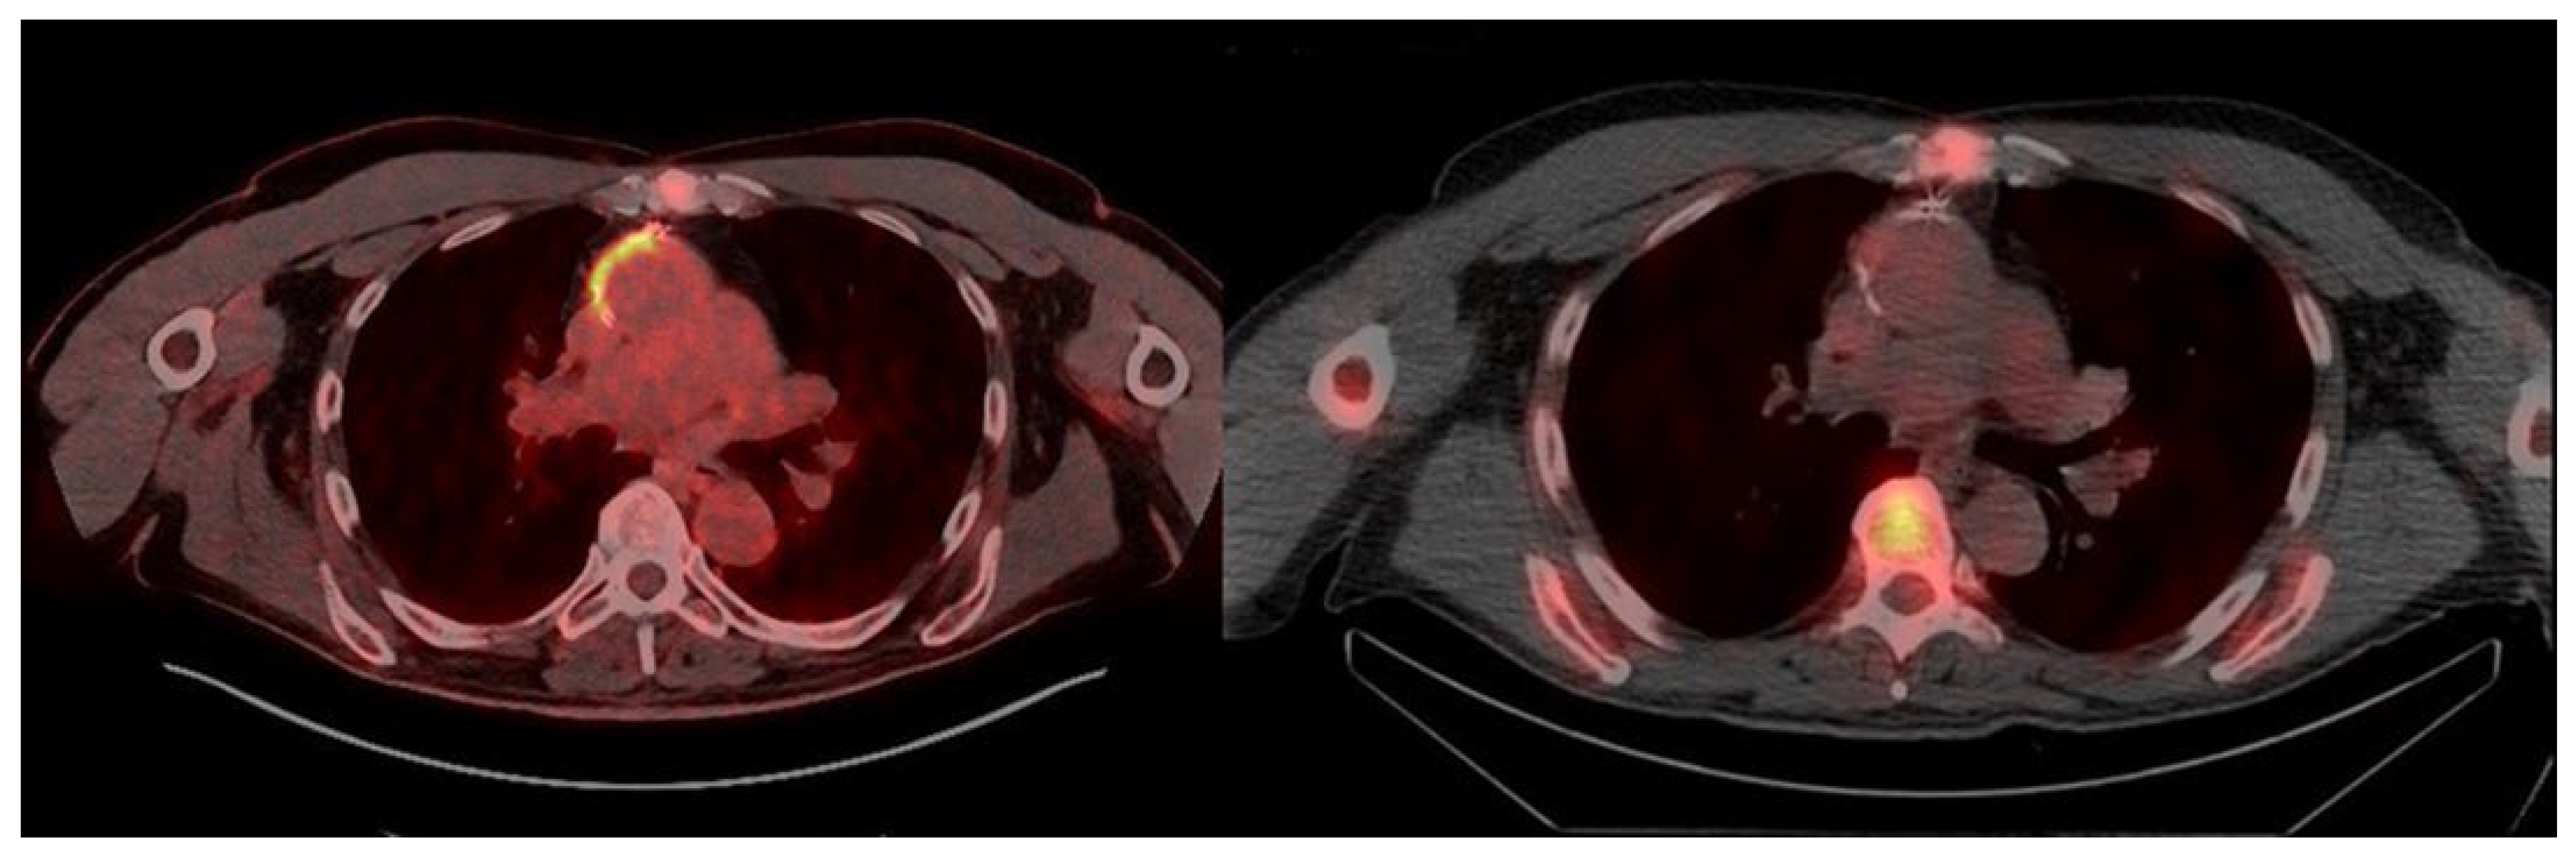

3. Results